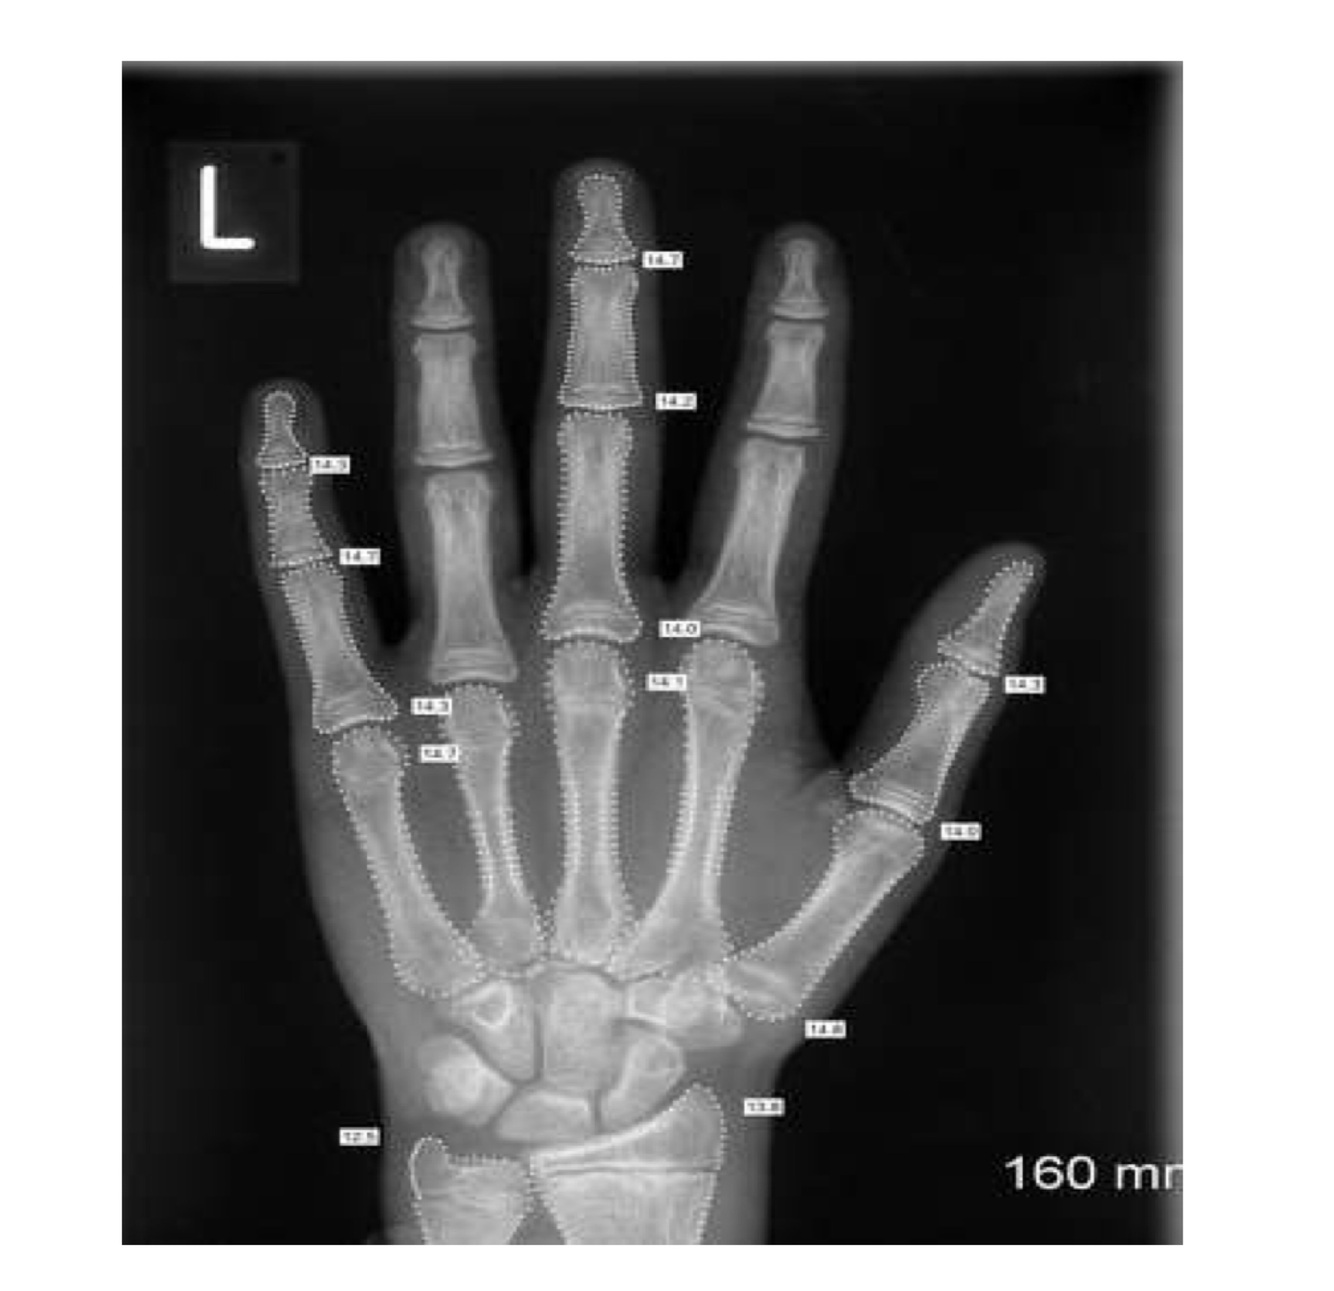

What is the purpose of assessing bone age in children?

To evaluate skeletal maturity and compare it with chronological age

What bone age pattern is typical in GHD?

**Delayed bone age** compared to chronological age and height age.